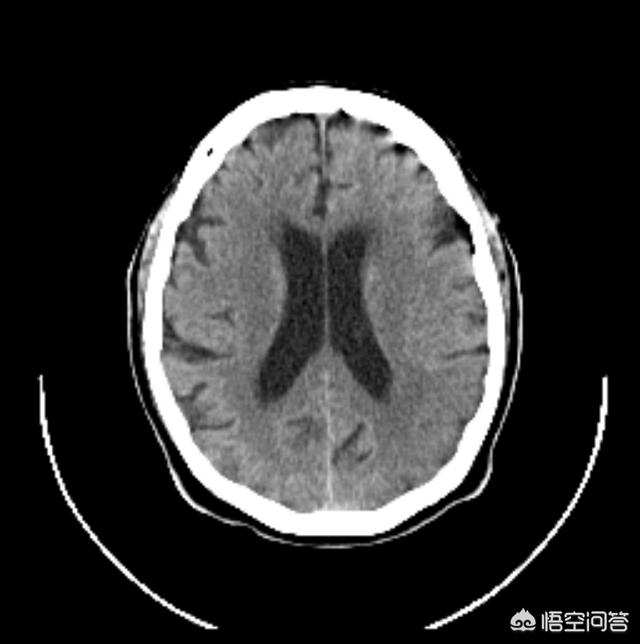

Bien sûr, l'infarctus cérébral ne se résume pas à ces symptômes, mais il s'agit des symptômes les plus typiques et les plus courants. S'il y a de tels symptômes, neuf fois sur dix il s'agit d'un infarctus cérébral (l'autre peut être une ischémie transitoire ou une hémorragie cérébrale), il faut se dépêcher d'aller au service des urgences d'un grand hôpital, le médecin doit vérifier le corps et faire un scanner de la tête qui sera tout à fait clair ! Cela ne retardera pas le meilleur moment pour la thrombolyse, rappelez-vous, le meilleur moment pour la thrombolyse est seulement 4,5-6 heures ah ! (Le temps peut être ajusté dans des circonstances particulières)